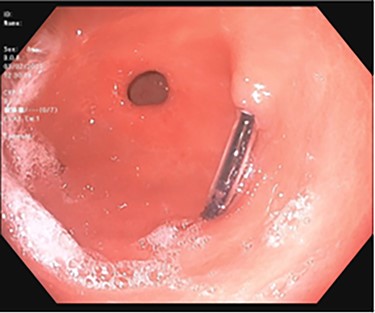

A 43-year-old incarcerated woman with borderline personality disorder and a long history of swallowing various foreign objects in periods of stress presented to the emergency department after swallowing a cup of bleach. Her surgical history was significant for multiple celiotomies for retrievals of purposefully ingested foreign bodies. During evaluation, she also admitted to swallowing an ink pen 3 weeks prior to swallowing the bleach for which she did not seek medical evaluation. She reported no food intolerance or changes in bowel function secondary to swallowing these objects. She presented with mild abdominal pain and cramping, and her vital signs and laboratory investigations were all within normal limits. Her abdominal exam was notable for mild tenderness to palpation diffusely. Computed tomography (CT) of the abdomen (Fig. 4) showed a linear foreign body in the distal gastric antrum penetrating the inferior wall and extending into the adjacent peritoneal fat. No free air or free fluid was appreciated. Initial esophagogastroduodenoscopy (EGD) was significant for mild erythema and edema to the esophageal and duodenal mucosa as a result of the caustic ingestion, and the pen was found to be deeply perforating the stomach antral wall with no associated ulcer or edema (Fig. 1). The depth at which the foreign body was lodged was uncertain, so there was concern for organ involvement outside of the gastric wall. Repeat EGD was done to assess for manifestations of esophageal, gastric or duodenal injuries from her caustic ingestion, and it revealed normal gastric mucosa (Fig. 2). A joint case was planned with the gastroenterology service for endoscopic foreign body retrieval, possible laparoscopic retrieval and gastric repair and possible open retrieval and gastric repair. The patient was taken to the operating room for the third EGD, which revealed spontaneous migration of the foreign body from the perforation site into the lumen of the gastric body (Fig. 3a). Additionally, there was spontaneous closure of the site of previous perforation (Fig. 3b and c). The ink pen was easily removed transorally using an endoscopic snare, and no further surgical intervention was required. After the procedure, the patient reported complete resolution of her abdominal pain and was able to tolerate a regular diet without problems.

Subsequent EGD 3 days later; gastric antrum with foreign body perforating through the gastric wall; normal gastric mucosa after ingestion of bleach.